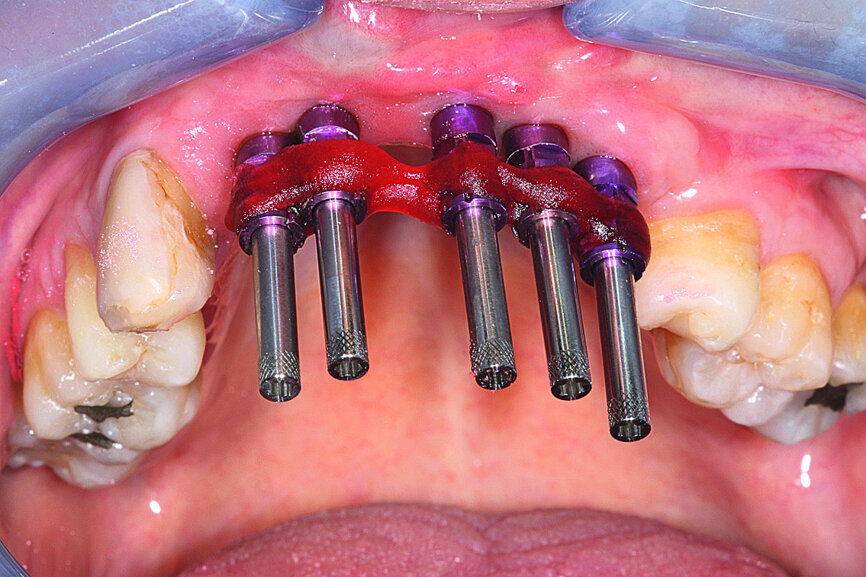

Implant placement

Local anaesthesia was administered and the bone site reopened. The site showed correct integration of the grafts, a notable increase in cortical bone and excellent vascularity throughout the site (Fig. 13). The sterilised surgical drilling guide was tested and showed that drilling would in fact be at the centre of the reconstructed bone ridge (Fig. 14).

After removal of the screws stabilising the grafts, the guide was placed and drilling (using physiological saline solution) completed. Five Aadva (GC Tech.Europe) self-tapping Grade 5 titanium microstructure implants were inserted by slow drilling (Fig. 15). Aspiration with physiological saline solution was not used at this time so that the first contact with the titanium oxide would be the patient’s blood, thus promoting the implants’ osseointegration. This specific implantation technique was validated by Brun et al. [6] All of the implants were equipped with threaded cover screws and the surrounding tissue was sutured (Fig. 16).

To minimise risks, the implants were left unloaded for four months, as immediate loading of a site such as this one could have proven to be problematic.